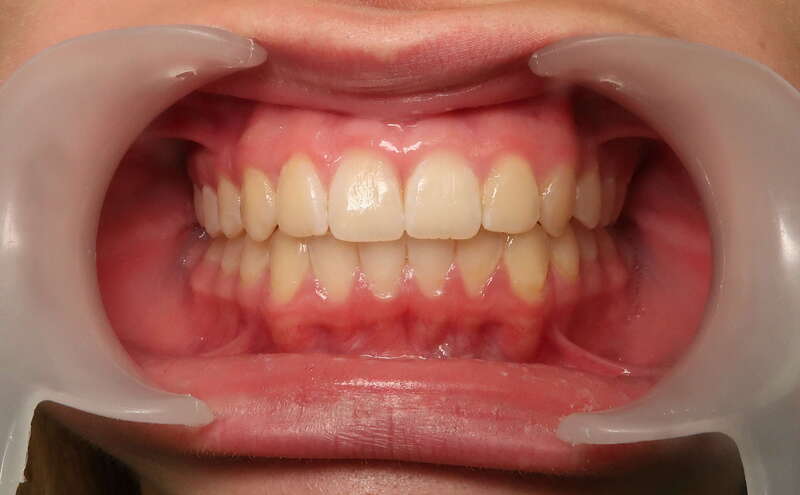

Cas n°1 traité par aligneurs - adolescent

Ce cas d’une adolescente illustre la correction d'une Classe II avec supraclusion par aligneurs. La stratégie thérapeutique a reposé sur une distalisation séquentielle de l'arcade supérieure. Ce mouvement précis a permis de reculer les dents maxillaires étape par étape pour annuler le surplomb (overjet) sans extractions.

Résultats clés :

• Correction fonctionnelle : Retour à un engrènement de Classe I stable et correction du recouvrement vertical.

• Esthétique restaurée : Harmonisation globale du sourire et du profil.

• Approche moderne : Un traitement discret, confortable et hautement prévisible.

Le résultat final montre une occlusion saine et un sourire parfaitement aligné, garantissant une santé dentaire et articulaire optimale pour l'avenir.

Avant

Après